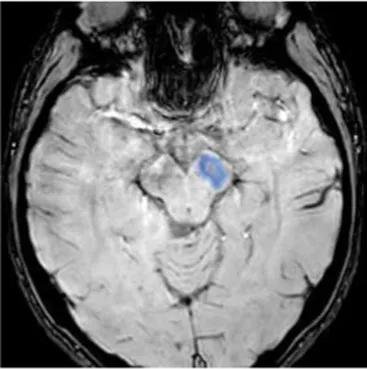

Studying the SNDG with conventional MRI, disruption to global functional connectivity has been revealed in the ipsi-lesional corticospinal tract and in the inter-hemispheric connections (corpus callosum), in the bilateral inferior fronto-occipital fasciculus and in the bilateral superior longitudinal fasciculus (34–36), in the ipsilateral thalamus, in the substantia nigra, hippocampus and in amygdala (37–39).

The involvement of these areas distal to the primary lesion defines the onset of cognitive and behavioral symptoms different from those primarily related to stroke area (36, 40). For example, involvement of the thalamus can lead to hyperalgesia; damage in the substantia nigra provokes Parkinson-like symptoms (slow movements, tremor, stiffness and difficulty with walking and balance); involvement of amygdala results in difficulty with memory processing and emotional reactions, whereas an involvement of hippocampus to memory impairment (Table 1).